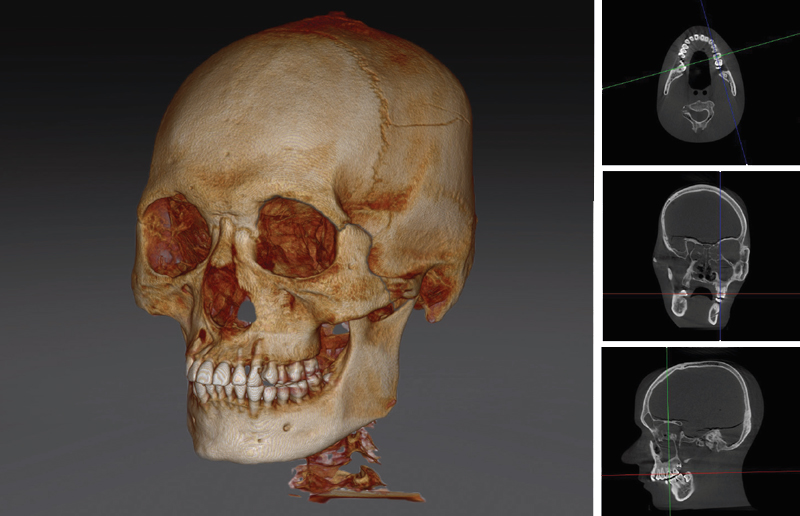

Возможности 3D КТ

Расширенные возможности сканирования с зонами 23х24 или 23х14.

PAPAYA 3D удовлетворит потребности врачей всех специальностей от эндодонтов до ортодонтов и даже пластических хирургов.

PAPAYA 3D подходит для сканирования головы и даже шеи.

Аппарат предназначен для широкого применения в различных областях, начиная от планирования отдельных зубных имплантатов с малой областью сканирования и заканчивая исследованием всего черепа с очень большой областью сканирования.

Зона сканирования – 23х24 см. Возможность оценки всех зон на одном снимке.

3D КТ

Технологии высокого разрешения в Компьютерной Томографии.

Зоны сканирования и функционал позволяющие поставить правильный диагноз даже в самых сложных клинических случаях.